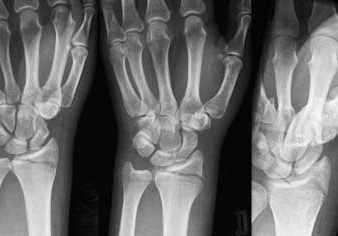

Так выглядит перелом запястья со смещением на рентгеновском снимке:

Снимок трещины в запястье:

На фото показаны осложнения перелома запястья со смещением, последствия отеков и окостенения: